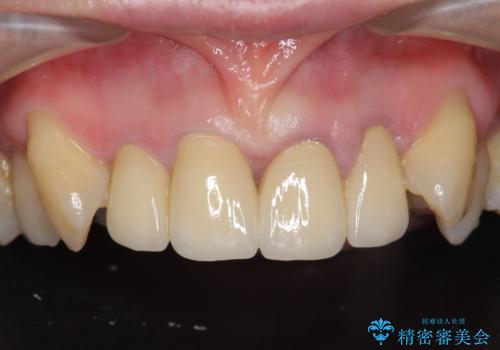

[ オールセラミッククラウン ] 前歯を自然な差し歯にしたい

![[ オールセラミッククラウン ] 前歯を自然な差し歯にしたいの症例 治療前](https://seimitsushinbi.jp/wp/wp-content/uploads/2022/07/3c5a785637ddccbb5d7fcd0b4a151157-500x350.jpg?v=1657095795)

![[ オールセラミッククラウン ] 前歯を自然な差し歯にしたいの症例 治療後](https://seimitsushinbi.jp/wp/wp-content/uploads/2022/07/f908365bae813c6881b43ba51882c130-1-500x350.jpg?v=1657095942)